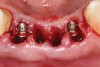

A 53-year-old male presented with localized advanced periodontal disease of the mandibular incisors. Teeth Nos. 23 to 26 exhibited Class II mobility because of advanced bone loss (Figure 1). The teeth had migrated out of position over the years, and a diastema had developed between No. 24 and No. 25 (Figure 2). The patient complained about the poor esthetic appearance of these teeth, and he was able to perceive their loss of strength on function as a result of their mobility.

Preoperatively, 1 g of amoxicillin was administered. Using local anesthesia (lidocaine 1:100,000 epinephrine), extractions of teeth No. 23 to No. 26 were performed without raising a flap and with gentle luxation to preserve the remaining facial osseous plate. The sockets were curetted prior to implant placement. A vacuum-formed surgical guide, fabricated based on a diagnostic wax-up of the desired tooth positions for the subsequent fixed prosthesis, was used during implant placement. Osteotomies were performed at sites No. 23 and No. 26 and positioned toward the lingual aspects of the sockets (Figure 3A and Figure 3B). Two tapered implants (OsseoTite™ 313, BIOMET 3i™, Palm Beach Gardens, FL) measuring 3.25 mm x 13 mm were placed. Conical prosthetic abutments (3-mm height) were used to facilitate joining the two implants in a screw-retained fixed partial denture (Figure 4). A laboratory-processed acrylic-resin provisional restoration was altered to allow connection to the temporary cylinders. The provisional was placed into the vacuum-formed surgical guide that was now used to maintain the provisional in the correct 3-dimensional position (Figure 5) while being attached to the temporary cylinders with acrylic resin intraorally. Once a sufficient amount of acrylic resin was placed to secure the cylinders to the provisional, it was removed from the mouth and its contours were completed at the laboratory bench (Figure 6A). The two central incisor sockets were grafted with small-particle allograft material (Puros® Allograft, Zimmer Dental, Carlsbad, CA) to maintain gingival architecture beneath two ovate pontics (Figure 6B). The provisional restoration was inserted and the screws tightened to 20 Nt-cm of torque.